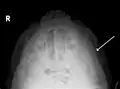

Side view of the skull.